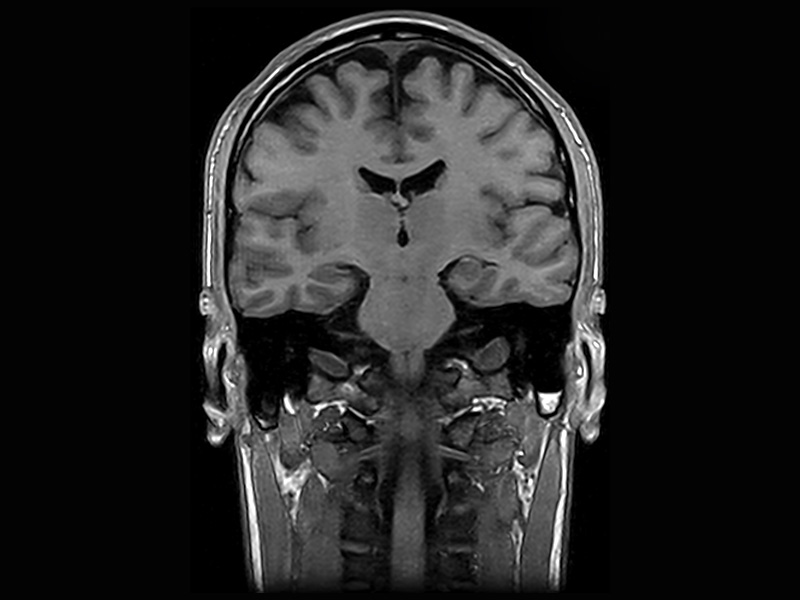

Klaustrofobní pacienti

Magnifico je ten správný systém pro klaustrofobické pacienty. Otevřený magnet z něj jednoduše dělá pohodlný zážitek z magnetické rezonance pro všechny pacienty, zejména děti. Magnifico navíc přichází s průhlednou hlavovou cívkou pro větší pohodlí pacienta.

Klinické snímky